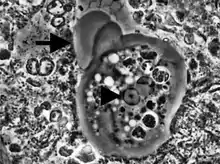

Entamoeba cells are small, with a single nucleus and typically a single lobose pseudopod taking the form of a clear anterior bulge. They have a simple life cycle. The trophozoite (feeding-dividing form) is approximately 10-20 μm in diameter and feeds primarily on bacteria. It divides by simple binary fission to form two smaller daughter cells. Almost all species form cysts, the stage involved in transmission (the exception is Entamoeba gingivalis). Depending on the species, these can have one, four or eight nuclei and are variable in size; these characteristics help in species identification.

Uninucleated trophozoites convert into cysts in a process called encystation. The number of nuclei in the cyst varies from 1 to 8 among species and is one of the characteristics used to tell species apart. Of the species already mentioned, Entamoeba coli forms cysts with 8 nuclei while the others form tetra-nucleated cysts. Since E. histolytica does not form cysts in vitro in the absence of bacteria, it is not possible to study the differentiation process in detail in that species. Instead the differentiation process is studied using E. invadens, a reptilian parasite that causes a very similar disease to E. histolytica and which can be induced to encyst in vitro. Until recently there was no genetic transfection vector available for this organism and detailed study at the cellular level was not possible. However, recently a transfection vector was developed and the transfection conditions for E. invadens were optimised which should enhance the research possibilities at the molecular level of the differentiation process.[10][11]